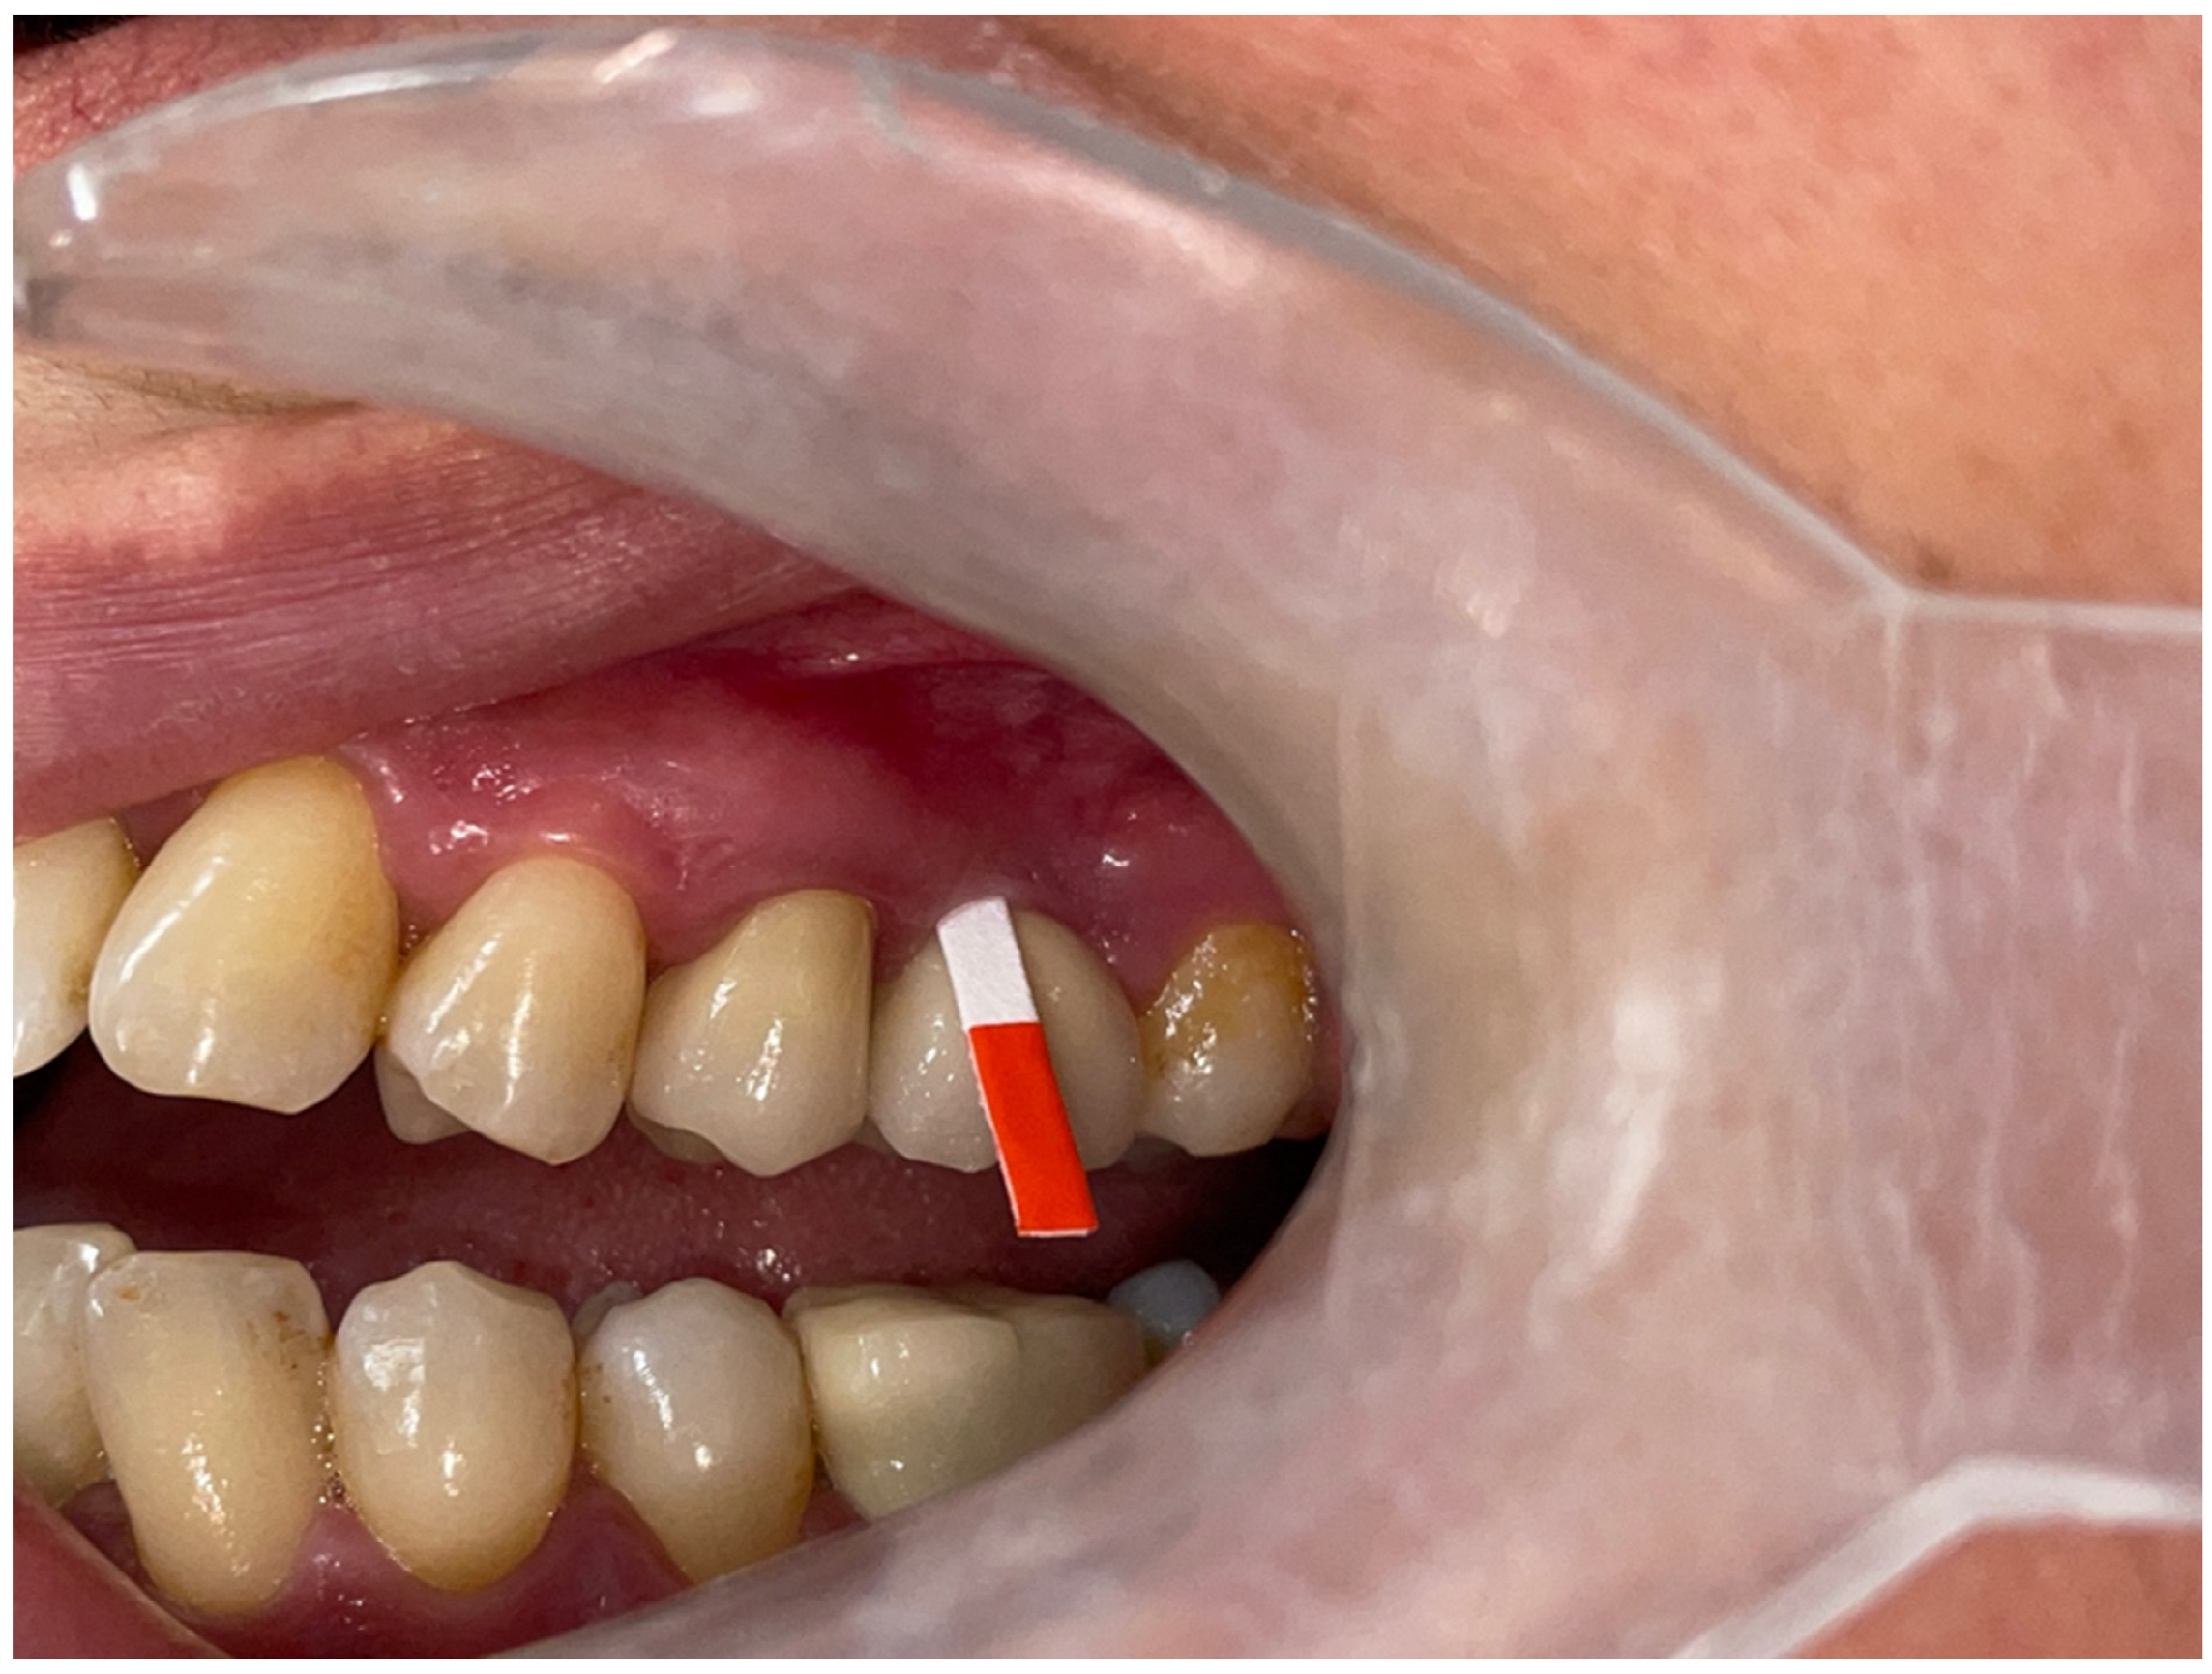

KMW and MT Measurements